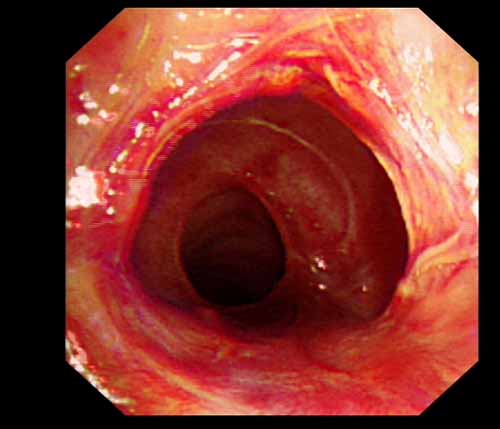

患者李某某,女,45歲,因氣管插管咳嗽、喘憋10天入院。頸部CT檢查示聲門下約20mm處氣管明顯狹窄,狹窄段長約26mm,最窄處直徑約4.4mm。支氣管鏡檢查見聲門下約2cm氣管呈漏斗狀縮窄,直徑約4-5mm,支氣管鏡無法通過。經(jīng)科室討論,決定行電子支氣管鏡下氣管球囊擴(kuò)張治療。與患者及家屬充分溝通并經(jīng)三方見證談話簽署知情同意書后,在患者持續(xù)吸氧、局麻下,科主任于世倫主任醫(yī)師帶領(lǐng)治療小組為患者實(shí)行電子支氣管鏡下氣管球囊擴(kuò)張術(shù)。手術(shù)過程順利,出血量很少,術(shù)后患者呼吸困難癥狀即可明顯緩解。10天后行二次擴(kuò)張,患者日?;顒訜o明顯喘憋,二次術(shù)后5天出院。

術(shù)前聲門下的漏斗樣狹窄口 術(shù)中球囊擴(kuò)張 術(shù)后擴(kuò)張開的氣管管腔